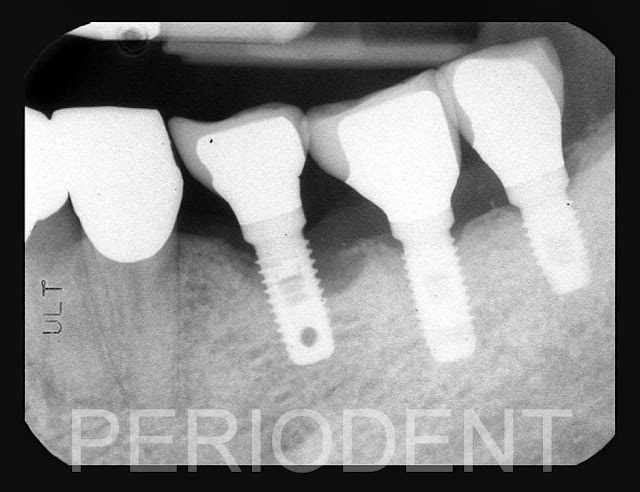

患者在國外已有植牙及假牙,但有牙齦退縮之情況

決定進行牙齦移植